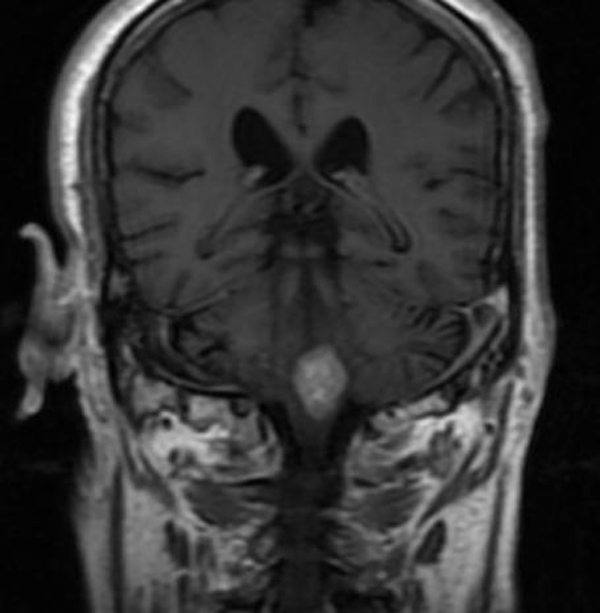

73岁的刘大爷因“言语不利、饮水呛咳及肢体无力”在当地医院以“脑梗塞”住院治疗10天,症状进行性加重,转入二一五医院进一步治疗,神经外科肖三潮教授、谢国强主任通过全院多学科会诊,经过充分评估患者病情后考虑,目前肿瘤占位效应明显,压迫延髓,导致患者呼吸功能紊乱,随时存在呼吸停止可能,唯有尽快手术切除肿瘤才能挽救患者生命,但延髓手术风险极大,术中患者随时存在呼吸心跳骤停可能,向患者家属充分告知手术必要性及危险性,征得家属同意后,12月27日,神经外科肖三潮教授、神经重症监护室谢国强主任、吴东飞主治医师在全麻下为患者行延髓占位切除术。

术中保留患者自主呼吸,严密检测生命体征变化,术中多次出现呼吸及心跳减慢,麻醉师予以兴奋呼吸等积极治疗,最终转危为安,历时6小时,手术顺利完成。术后患者神志清楚,术后三天脱机,右侧肢体功能正常,左侧肢体肌力同术前(3级),目前正在逐步康复中。